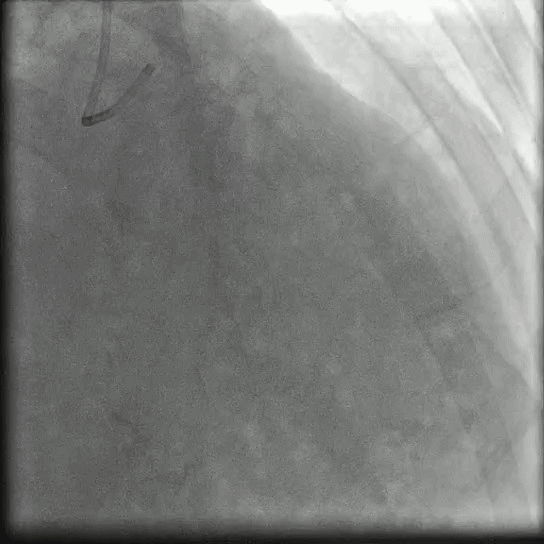

心臟檢查方式四:冠脈造影

“此項(xiàng)目能檢查房間里的水管堵沒堵,因?yàn)楣茏佣际氰F皮包著,里邊銹成啥樣造影就能看見。”

冠狀動(dòng)脈造影是目前診斷冠心病最直接、最可靠的方法。對(duì)于其他無創(chuàng)檢查方法都不能確診的患者,冠脈造影檢查是唯一一種可提供有力診斷依據(jù)的手段。推薦閱讀: